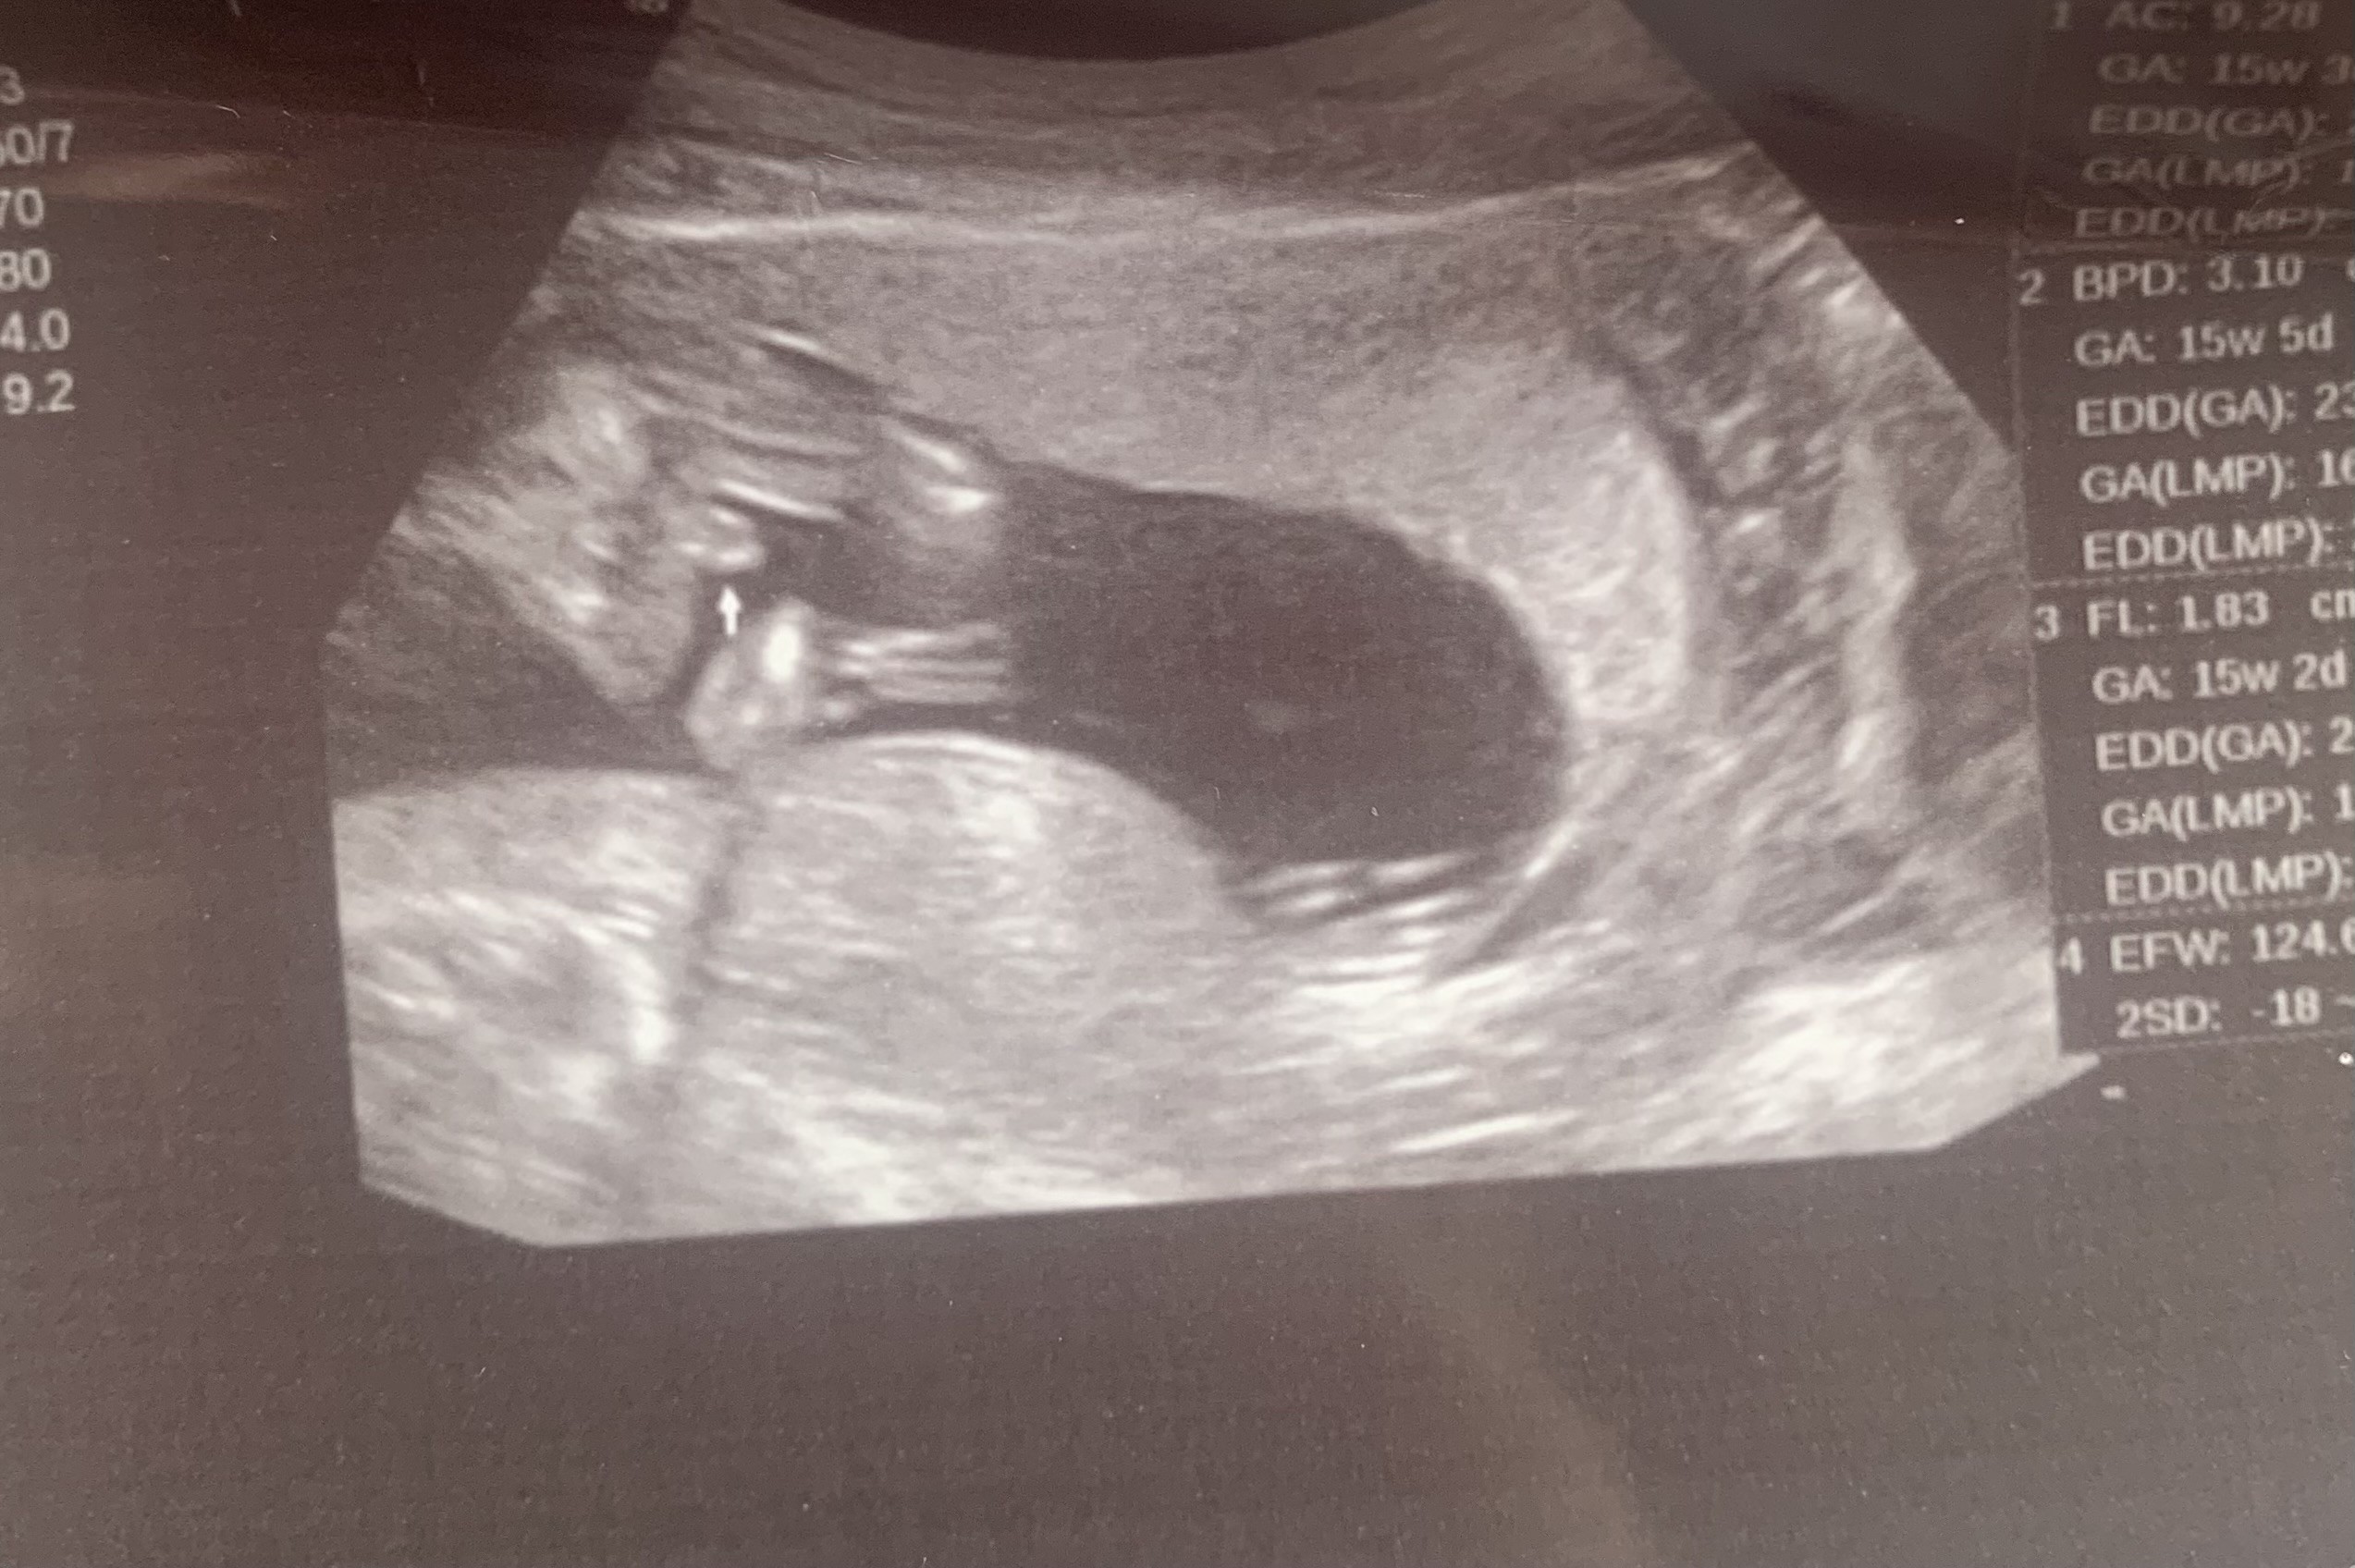

To ja się podepnę

Czy na tym zdjęciu widzicie wyrostek płciowy? Na prenatalnym wyszła dziewczynka a dziś ginekolog powiedział że obstawia chłopca. Nie mogę się z tym pogodzić, nawet zrobiłam test z sody 🙄

15w5d

• IMG_5540.jpeg

IMG_5540.jpeg

713,1 KB · Wyświetleń: 170

W 15 tygodniu zaczynają już formować się narządy z wyrostka. Zresztą wyrostek sprawdza się w przekroju poprzecznym, a tu jest ujęcie nocnikowe. Według mnie z tego ujęcia jeszcze za wcześnie. Mogą z tego wyjść zarówno narządy chłopiece jak i żeńskie, chociaż też obstawiałabym bardziej chłopca.